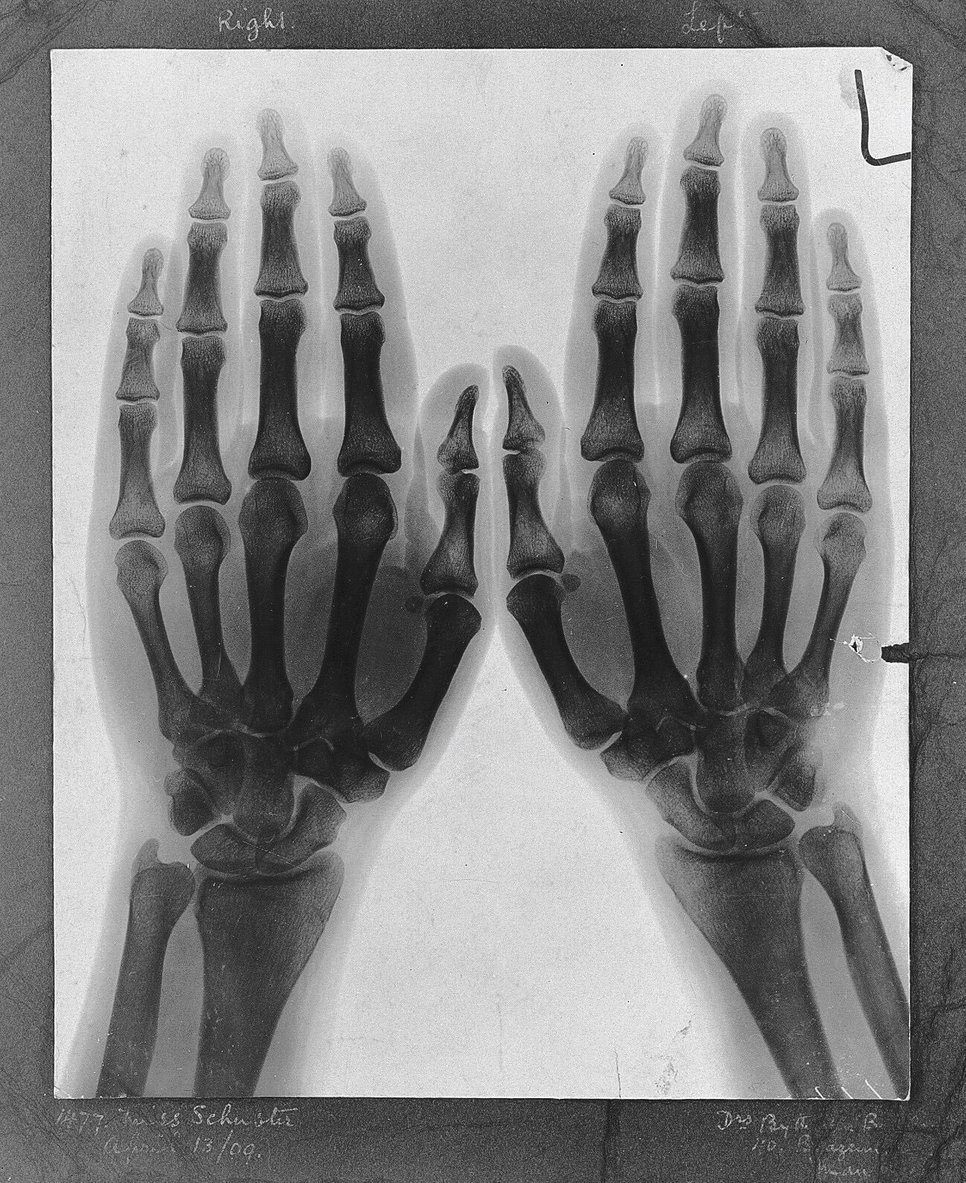

How do we depict the invisible? What lies beyond the visible spectrum? European scientists and artists grappled with these questions at the end of the nineteenth century. Often described as the “frenzy of the invisible,” this era was marked by new understandings of the possibilities of invisible worlds. X-rays with spectacularly small wave-lengths outside the capacity of human vision, sound and radio waves that preserved and transmitted the voice, and the prospect of proving supernatural phenomena all contributed to this “frenzy,” with both artists and scientists seeking the means to represent these newfound invisible presences. This art historical project focuses on the technologies which were used in order to track the visual history of the invisible spectrum and the shifting understanding of what it meant to “represent” something. It is organized around overlapping areas of rupture within the visible spectrum that occupied scientists and artists: sound and the waveform, the medicalized body, and the supernatural. Recordings of the invisible world opened possibilities to materially register what eluded eye-sight, thereby unsettling the disciplinary boundaries between art, science, and technology in the late Victorian era.